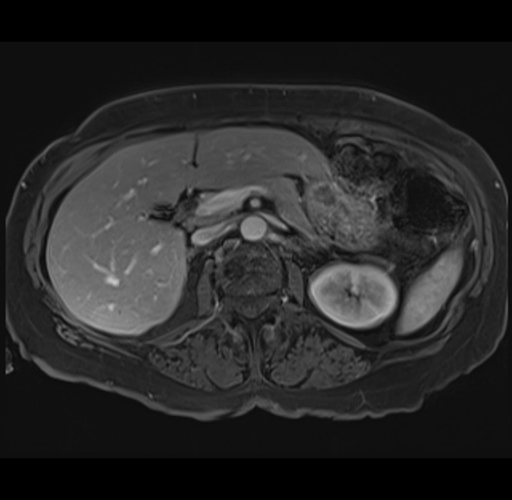

Axial Venous

MRI T1